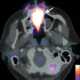

Lesion of hard palate